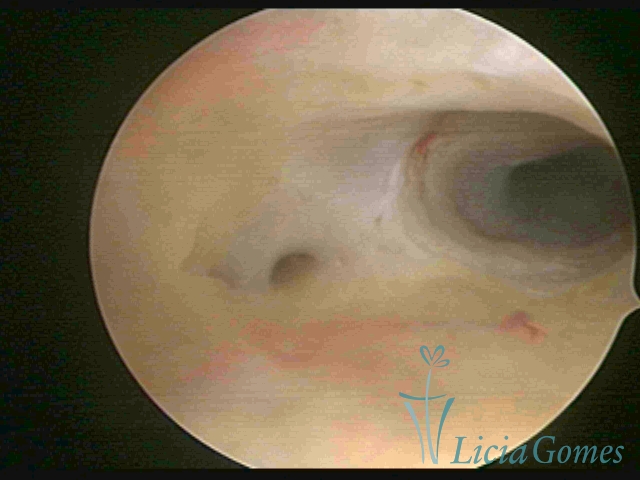

Segunda porção ou setor médio

No terço ou setor médio do canal cervical perdemos o detalhe das papilas, sendo possível a visualização de pregas e criptas. Normalmente observamos os sulcos longitudinais, que são os tecidos mais compactos, com a superfície mais vascularizada, cujos vasos seguem o seu trajeto.